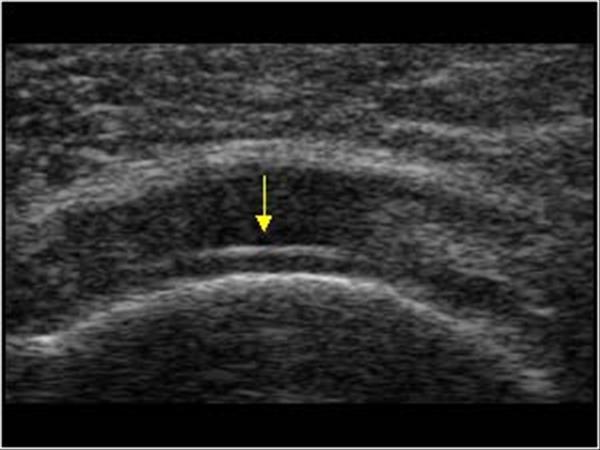

3. 연골 경계부 징후(Cartilage interface sign)란 무엇인가? 이러한 환자가 가지고 있는가?

☞ 회전근개 파열부 아래의 관절액과 유리연골 사이의 고에코 경계부는 초음파의 증가된 투과성을 가진다. 그렇다.

△ 연골 경계부 징후(Cartilage interface sign)

회전근개 전층파열은 저에코성 또는 무에코성의 결손 구조로 나타나는데, 액체가 찢어진 힘줄을 대체한 것이다. 이 액체는 연골을 고에코성으로 강조하는 초음파의 투과도가 두드러지게 나타난다. 이는 이중 피질 모양을 만들어 내는데, 두개의 고에코 평행 선 또는 연골경계부 징후를 가진다. 압박은 점액낭주위 지방을 힘줄 틈으로 만들 수 있는데, 이를 새깅 점액낭주위 지방 징후(sagging peribursal fat sign)이라 부른다. 힘줄의 비가시화는 매우 크고 수축된 힘줄을 암시한다. 근육의 위축은 근육의 전반적인 에코발생도를 증가시킬 수 있다.